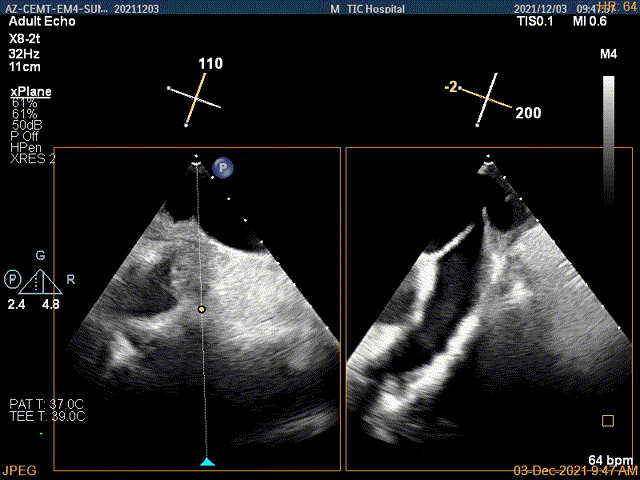

术中及术后即刻超声评估

3D视图菲薄的卵圆窝,穿刺点位近似于3点位

3D视图下大鞘位置及长度测量

4Ch验证前后叶抓捕后有典型的bouncing征

x-plane平面测量确认后叶抓捕长度大于6mm